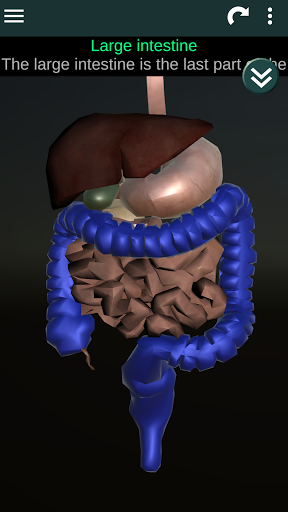

* Sistem pencernaan, termasuk lambung, usus kecil, usus besar, dan animasi sistem ini.

* Deskripsi masing-masing organ.